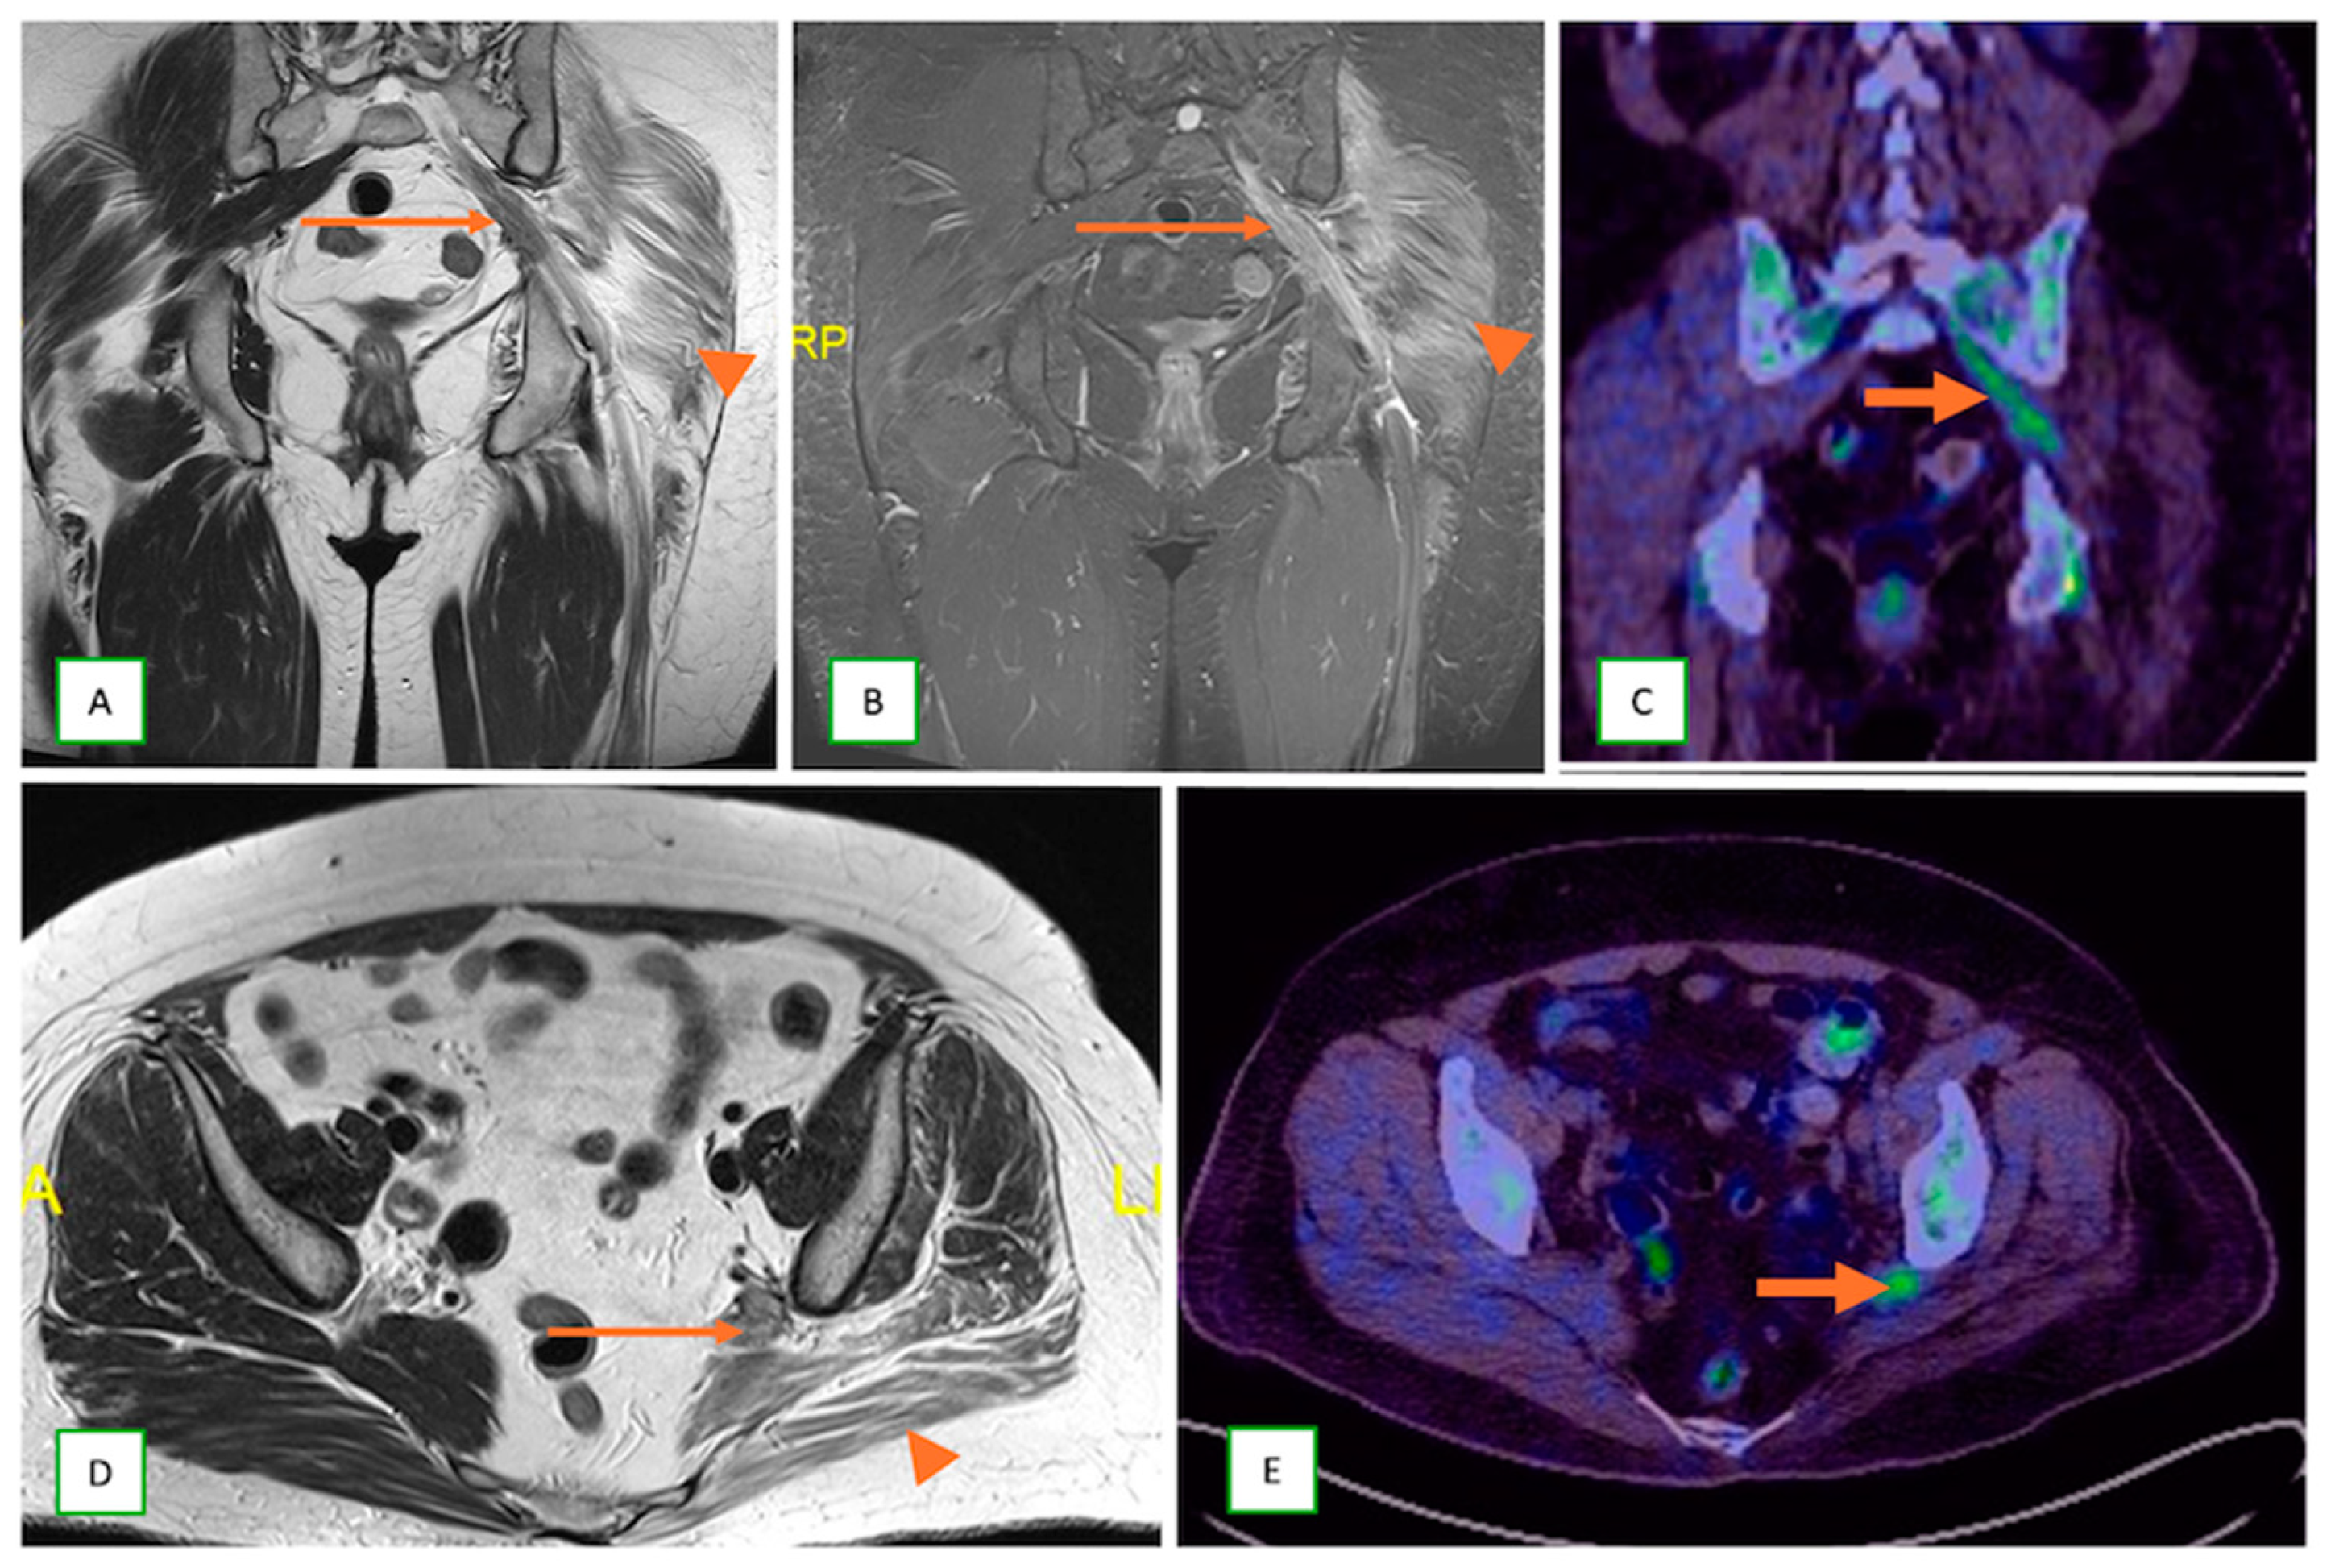

- Metastatic lesions: These include perineural spread of the tumor or metastasis to peripheral nerves by an adjacent or distant primary tumor. They are commonly observed with head and neck cancers, such as squamous cell carcinoma. They typically appear as linear thickening and enhancement extending along the course of the affected nerve on MRI with end muscle edema and appear FDG-avid on PET-CT [66] (Figure 24 and Figure 25).

- Primary Sarcomas: Soft-tissue sarcomas are uncommon, accounting for just over 1% of adult malignancies. Synovial sarcoma, clear cell sarcoma, and epithelioid sarcomas are known to involve peripheral nerves. CT/MR reveals a large soft tissue mass with areas of necrosis or calcification and heterogeneous contrast enhancement. F-18 FDG uptake is useful for both tumor staging and treatment assessment (Figure 26, Figure 27 and Figure 28).